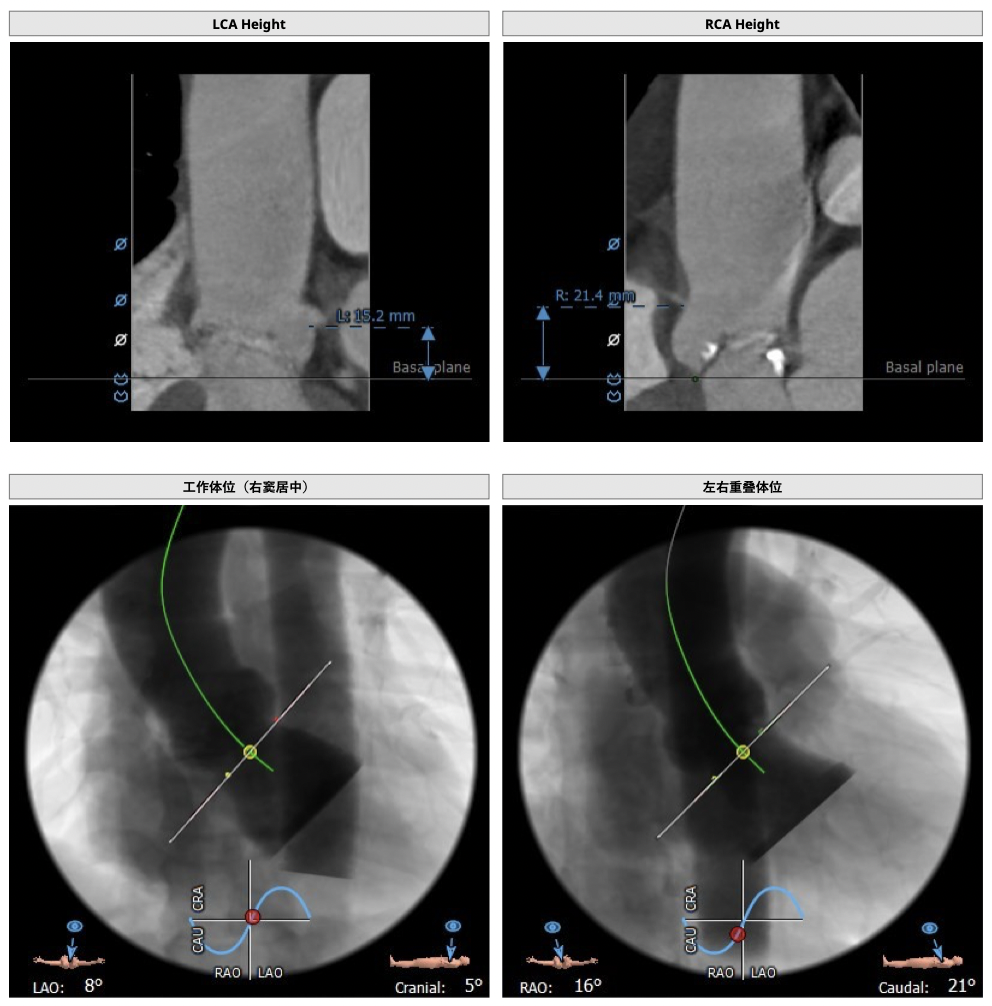

主动脉CT

图片

手术策略

难点分析:

*功能型二叶瓣,瓣叶增厚,重度钙化,瓣环及左室流出道层面仍可见钙化,左右可见钙化融合,瓣膜释放后发生瓣周漏的风险较高,瓣膜释放后容易移位。

*左右股动脉较细,直径小于6mm, 双侧髂动脉-股动脉走形迂曲,可见明显钙化,术中操作需谨慎轻柔,注意血管并发症的发生。

*左室腔较大,术中需注意液体管理。

制定策略:

经分析研判,拟从右侧股动脉穿刺入路,使用22mm球囊预扩,选用L26号的VenusA-Valve瓣膜,采用VenusA-Plus可回收输送系统进一步确保手术安全,瓣膜释放后结合造影和超声情况,决定是否后扩。